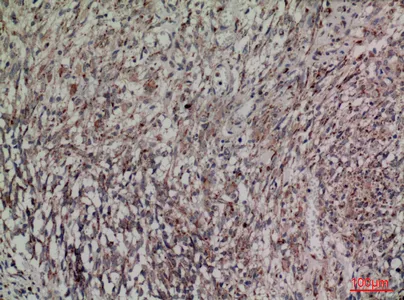

FOXP1 Rabbit Polyclonal Antibody

Cat: APRab11113

Size1:50μl Price1:$118

Size2:100μl Price2:$220

Size3:500μl Price3:$980